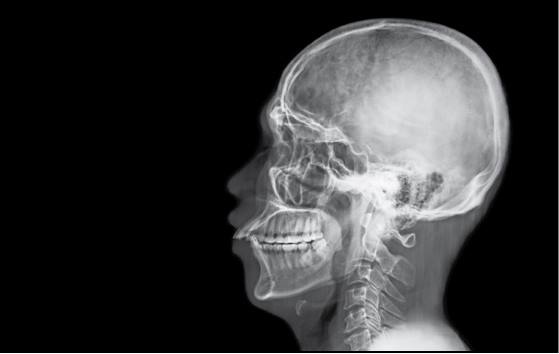

Глядя на природу человека, часто отделяют биологическое (телесное) от психического. Но психика является продуктом деятельности головного мозга. Равно как и все процессы, в том числе болезненные, которые происходят в организме, отражаются на деятельности психики. И существует целый пласт психических расстройств, которые связаны с системными (то есть поражающими все части организма) заболеваниями. Моя врачебная практика началась с отделения сочетанной психической и соматической (телесной) патологии, и именно там связь между телом и духом ощущалась наиболее остро.